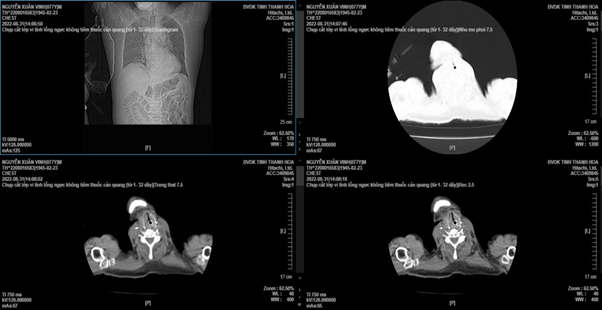

Hình ảnh khối phình trên phim chụp CT-scanner trước và sau can thiệp

Khối phình động mạch chủ bụng đoạn dưới các động mạch thận, đường kính khoảng 7-8 cm, bị vỡ 1 đoạn dài khoảng 4cm. Khối phình vỡ vào sau phúc mạc, tạo thành khối máu tụ khổng lồ chiếm hơn 1/2 bụng bên trái, bóc tách toàn bộ phía sau đại tràng xuống, hố thận trái, cơ thắt lưng chậu trái và lan rộng đến các động mạch chậu hai bên. Các bác sĩ cắt bỏ hoàn toàn khối phình động mạch chủ chậu, tái lập lưu thông động mạch chủ chậu với ghép mạch máu nhân tạo dạng chữ Y, nối giữa động mạch chủ – chậu trái và chủ – đùi bên phải.